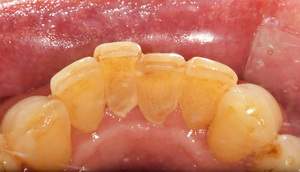

歯石除去

治療前

治療後

| 年齢 | 40歳・男性 |

| 主訴 | 歯石をとりたい |

| 治療内容 | 歯石除去 |

| 治療期間 | 30分 |

| 費用 | 約2,000円 |

| リスク・副作用 | ・歯ぐきの炎症が強いと歯石を取る際に出血することがあります。 ・処置後に歯がしみることがあります。 ・歯と歯の間に隙間ができるので、息が漏れ発音しにくいと感じることがあります。 ・歯ぐきの炎症が軽減すると歯ぐきが引き締まり、歯が長く見えることがあります。 |